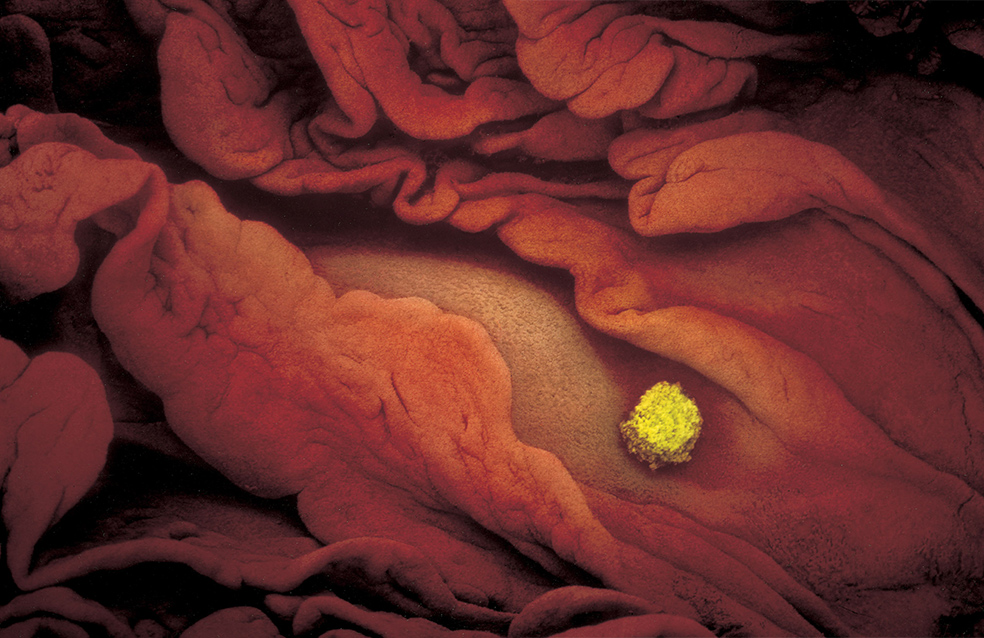

Un óvulo en la trompa de Falopio, donde permanece durante 24 horas, listo para ser fecundado por un solo espermatozoide.